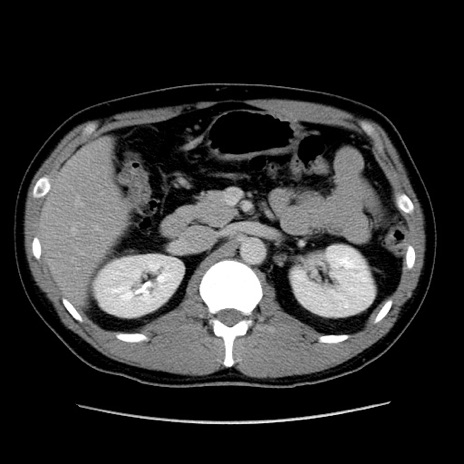

症例4(横断像)

【症例】30歳代男性

【主訴】腹痛、嘔吐

【現病歴】昨晩から突然の腹痛あり、その後嘔吐、軟便も出現。腹痛が改善しないため救急搬送となる。2日前にしめ鯖の食事歴あり。

【身体所見】意識清明、苦悶様、BP 135/90mmHg、BT 35.7℃、腹部:平坦、やや硬、心窩部〜臍部に自発痛、圧痛あり、筋性防御+、反跳痛-

【データ】WBC 8100、CRP 0.57